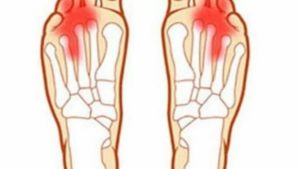

1. Артроз ступни

К болезням суставов дегенеративного характера относится артроз стопы. Изменения затрагивают их хрящевую ткань, кости и мышечные волокна. Наиболее часто зона с артритными изменениями располагается около сустава большого пальца ноги – плюснефалангового.

Боли в стопе под пальцами являются одним из признаков артроза суставов ступни. Пациенты описывают другие его симптомы:

- нога и палец болят в процессе ходьбы или при длительном стоянии, ощущения усиливаются при увеличении нагрузки на конечности;

- ноги быстро утомляются, в них ощущается сильная усталость;

- кожа над пораженной зоной приобретает явную отечность, изменяет цвет – становится красной, горячей на ощупь;

- работа сустава сопровождается слышимым хрустом;

- нога и палец по-особому реагируют на изменение погодных условий – сильно болят;

- появляются мозоли, костные наросты, утолщение сустава;

- движения сустава ограничиваются из-за боли и нарушения работоспособности мышц, двигательная активность особенно затруднена после ночного отдыха;

- заметно изменяется походка, человек заметно хромает, переваливается из стороны в сторону.

Боль под пальцами на ноге описывается как жгучая, ноющая. Она зависит от степени и разновидности артроза ступни. Кроме анализа анамнеза, диагностировать заболевание помогают лабораторные исследования (для определения воспаления), оценка размеров стопы, рентгенография. Визуализировать состояние хрящей, костей, мышц можно при помощи МРТ или КТ.